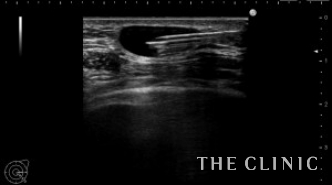

本日は4年前に他院でヒアルロン酸豊胸を行った後にしこりになった方を紹介します。

エコーでは大きなしこり以外にも小さなしこりを多数認めました。

一つ一つエコー下にヒアルロニダーゼで溶解して吸引除去します。

小さなしこりも除去します。

除去後ヒアルロン酸は消失しました。

ヒアルロン酸注入によるしこりのエコー診断カルテ